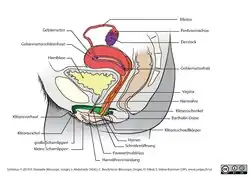

Die Vagina ist ein dehnbares, muskulös-bindegewebiges, mit einer Schleimhaut ausgekleidetes Organ im Bauchraum. Sie liegt etwa in der Beckenachse[1] und durchquert hier den Beckenboden.[2] Die Vagina verbindet den Scheidenvorhof mit der Gebärmutter (Uterus). Der Gebärmutterhals ist um etwa 90 Grad nach vorn abgeknickt und folgt damit nicht der durch die Vagina vorgegebenen Richtung.

Hintere und vordere Vaginawand

Die hintere Vaginawand (Paries posterior vaginae) ist durch die Lage des Uterus etwas länger als die vordere Vaginawand (Paries anterior vaginae).[6] Im ungedehnten Zustand ist sie durch das Parakolpium abgeflacht, die vordere und die hintere Wand berühren sich, sie werden von den Nachbarorganen komprimiert, und umschließen das Lumen der Vagina, das einen H-förmigen Spalt bildet und dadurch eine Entfaltung ermöglicht, ohne große Spannung zu erzeugen.[7] Die Hinterwand (Dorsalwand) der Vagina ist durch Bindegewebe (Septum rectovaginale) mit dem Mastdarm und die Vorderwand über das Septum vesicovaginale und das Septum urethrovaginale mit der Harnblase und der Harnröhre verbunden.[2] An der vorderen und hinteren Vaginawand befinden sich zudem Querfalten, die als Scheidenrunzeln (Rugae vaginales) bezeichnet werden und eine vordere und eine hintere Runzelsäule bilden (Columnae rugarum anterior et posterior). Diese verstärken beim Geschlechtsverkehr die Reizwirkung und stellen zugleich eine Dehnungsreserve für die Geburt dar.[8]

Uterusseitig ragt die Portio vaginalis uteri des Gebärmutterhalses in die Vagina vor. Diese wird von der Vagina so umfasst, dass sie zwischen dem tiefen, hinteren (dorsalen), sowie dem kleineren seitlichen und dem vorderen (ventralen) flachen Scheidengewölbe (Fornix vaginae) liegt.[2] Das hintere Scheidengewölbe reicht bis an den Douglas-Raum heran,[2] einer taschenförmige Aussackung des Bauchfells und damit der tiefste Teil des Bauchraums zwischen Mastdarm und Uterus.

Muskulatur, Blutversorgung und Nerven

Neben der glatten Muskulatur in der Vaginawand wird die Vagina von quergestreiften Muskeln umgeben, die gitterartig angeordnet sind. Der Musculus pubococcygeus, ein Anteil des Musculus levator ani, ist ein Muskel des Beckenbodens. Die Muskeln beider Seiten (Levatorschenkel) umfassen die Vagina wie eine Schlinge und ermöglichen eine willkürliche Verengung derselben.

Die Blutversorgung der Vagina erfolgt über die Arteria vaginalis aus der Arteria iliaca interna, die unterhalb der Arteria uterina entspringt. Hinzu kommen Versorgungsäste der Arteria vesicalis inferior und der Arteria pudenda interna. Das die Vagina umgebende Venengeflecht (Plexus venosus vaginalis) wird über die Vena uterina abgeleitet.[7] Die Lymphe des oberen Teils der Vagina fließt über die Nodi lymphatici iliaci interni in die Lendenlymphknoten, vom unteren Teil in die Leistenlymphknoten (Nodi lymphatici inguinales superficiales).[6]

Die Nervenversorgung der Vagina erfolgt durch den Plexus uterovaginalis.[6][7][12]